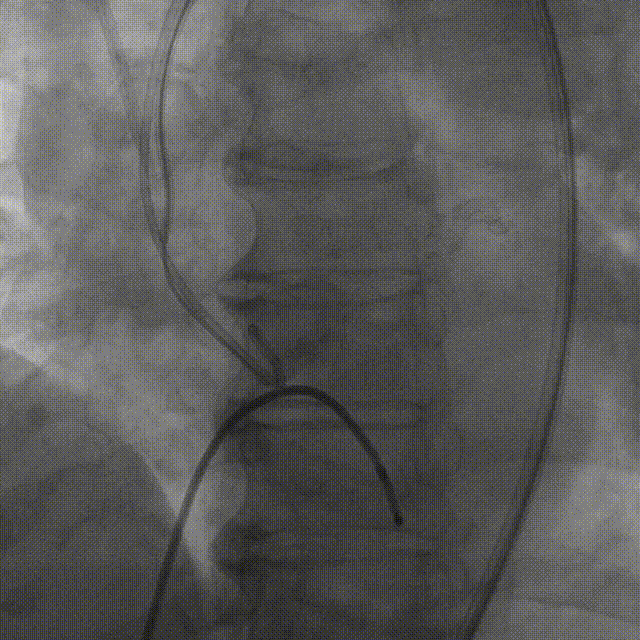

TaurusNXT植入过程

术中影像

主动脉根部造影

TaurusAtlas 18mm球囊预扩张

瓣膜释放至工作位造影

最终造影